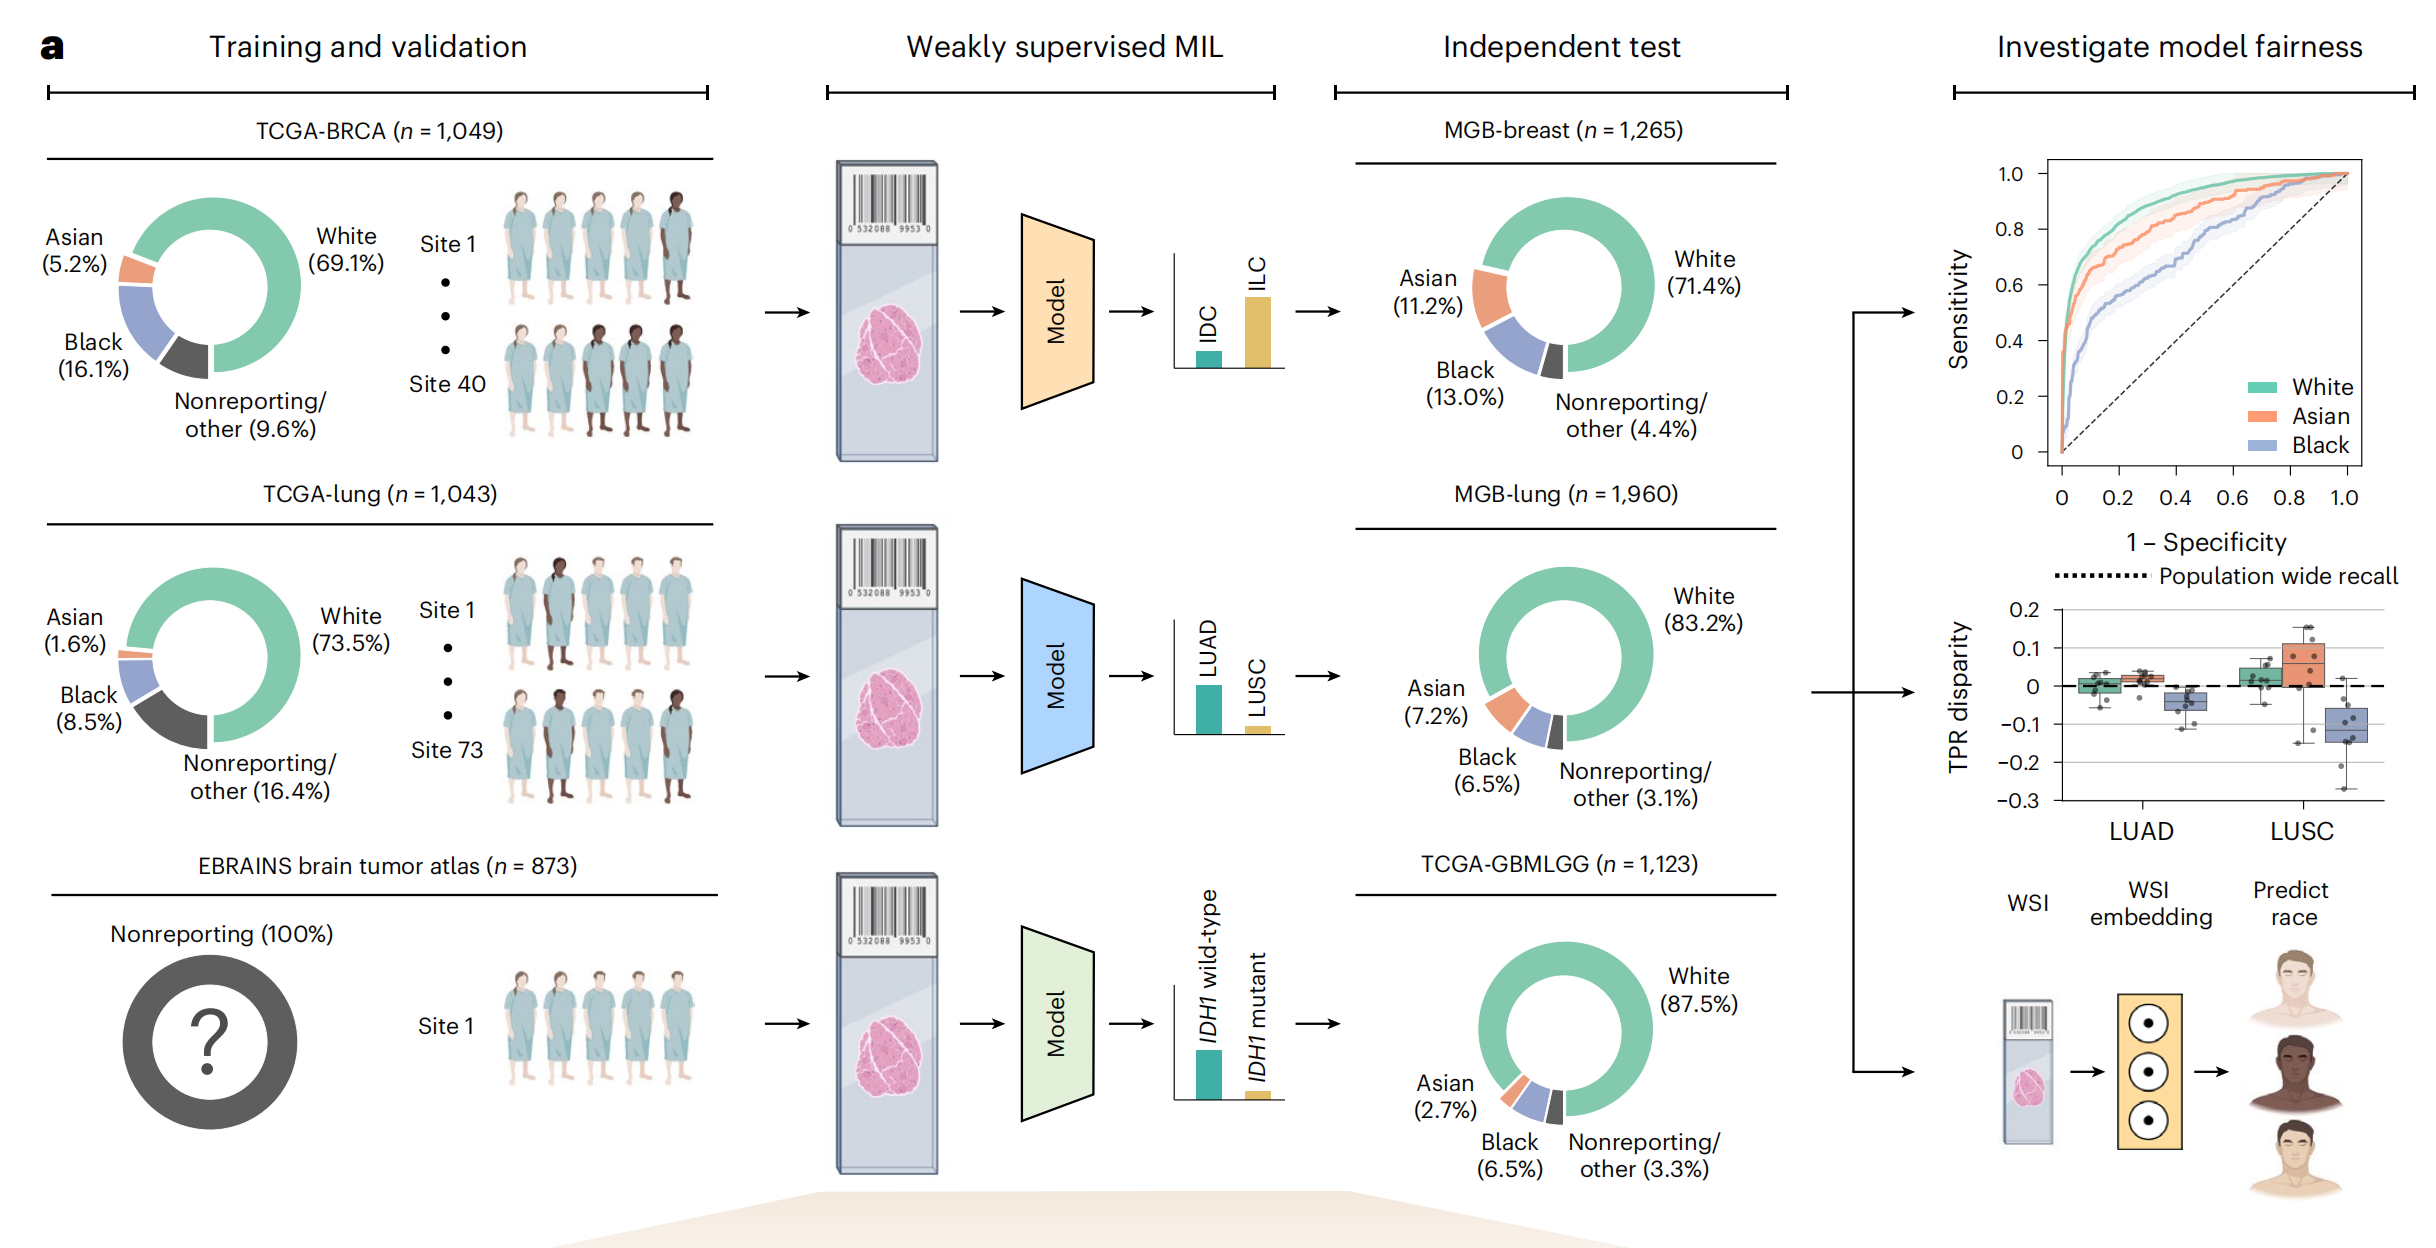

这篇文章发表在《Nature Medicine》2024年4月号上,题为《Demographic bias in misdiagnosis by computational pathology models》,作者包括Anurag Vaidya, Richard J. Chen, Drew F. K. Williamson等多位研究人员。文章主要探讨了在计算病理学模型中,人口统计因素对性能的影响,尤其是这些模型在对乳腺癌和肺癌亚型分类以及胶质瘤中IDH1突变预测时,对不同人群可能存在的偏见和误差。

文章指出,尽管计算病理学系统获得了越来越多的监管批准,但基于深度学习的系统经常忽视人口统计因素对性能的影响,可能导致偏见。这一问题尤为重要,因为计算病理学依赖于大型公共数据集,而这些数据集往往不能充分代表某些人群。研究使用了来自癌症基因组图谱(The Cancer Genome Atlas, TCGA)和EBRAINS脑肿瘤图谱的公开数据,以及内部患者数据,展示了在不同人群之间存在显著的性能差异。

研究结果表明,使用常见的建模方法时,白人和黑人患者在乳腺癌亚型分类、肺癌亚型分类以及胶质瘤中IDH1突变预测方面的性能差距分别为3.0%、10.9%和16.0%。研究发现,通过自监督视觉基础模型获得的丰富特征表示可以减少群体间性能差异。即便如此,自监督视觉基础模型并不能完全消除这些差异,这突显了在计算病理学中持续需要努力减轻偏见。

文章还讨论了数据特征、模型架构和偏见缓解策略对模型公平性和性能的影响,并建议监管和政策机构在评估指南中整合人口统计分层评估。此外,研究还发现,即使在考虑了与人群相关的数据特征后,不同种族群体之间的性能差异仍然存在,这表明需要在计算病理学中进一步研究和解决这些差异。

文章最后强调,为了提高计算病理学模型的公平性和性能,需要采取多种措施,包括使用自监督学习、改进数据预处理技术、实施偏见缓解策略,并确保在不同人群中进行充分的模型评估和测试。

Fig. 1 展示了在研究中使用的三个数据集(TCGA、MGB和EBRAINS脑肿瘤图谱)的特征、研究中使用的公平性指标以及建模选择。

以下是对图的详细分析:

a 部分展示了用于研究的三个数据集的组成,包括它们包含的用于诊断算法研究的幻灯片数量。这些数据集用于调查在最小化行动学习(MIL)幻灯片级别癌症诊断算法中的人口统计偏差,具体是针对乳腺癌和肺癌亚型分类以及胶质瘤中IDH1突变预测。研究使用了种族分层的ROC AUC(接收者操作特征曲线下面积)、TPR差异(真正例率差异)和独立测试队列上的种族预测来调查差异。

b 部分描述了MIL计算病理学研究中使用的深度学习(DL)管道的不同阶段,包括组织分割和贴片、使用贴片编码器映射到低维表示,以及分类。图中还展示了与公平性相关的技术,包括控制批次效应和测试集偏差、建模选择和偏见缓解策略。

c 和 d 部分介绍了研究中使用的两种常见的偏见缓解策略。c 部分描述了重要性加权(IW),这是一种通过与它们在总人口中的大小成反比地对种族群体中的患者进行采样,以确保公平代表性的方法。d 部分描述了对抗性正则化(AR),这是一种通过使嵌入对种族不可知来缓解偏见的策略。通过最大化辅助种族分类器的损失来实现这一点。

总体而言,Fig. 1 提供了对研究中使用的数据集、评估方法和偏见缓解策略的全面视图,并通过可视化手段展示了不同技术对减少种族间性能差异的潜在影响。